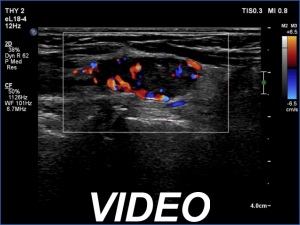

Second examination (second row of images):

Clinical data: The patient came to a routine follow-up.

Palpation: no abnormality.

Laboratory tests: TSH 3.84 mIU/L on daily 75 microgram levothyroxine.

Ultrasonography. The presentation of the thyroid was essentially the same. The mass in question became smaller. This was avascular and proved to be hard on elastography.